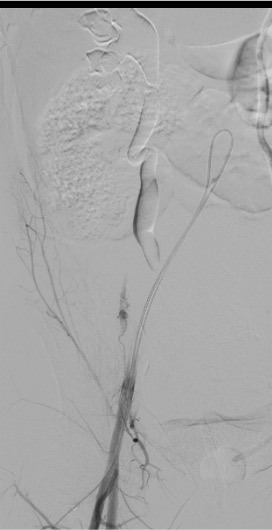

- Post-delivery: uterus dramatically enlarged with hypertrophied, tortuous uterine arteries — may extend well cephalad above the umbilicus

- Postpartum UA is typically large and easy to catheterize, but also prone to spasm

- Adjust imaging field of view: postpartum uterine arteries extend much more cephalad than typical pelvic arteriography

Contralateral anterior oblique (CAO, ~30 degrees) best shows the IIA origin. Steep ipsilateral oblique (30–45 degrees) differentiates anterior and posterior divisions and isolates the uterine artery. Use a fast filming rate (4–6 frames/sec) with injection rates of 7–10 mL/s for 2–4 seconds for pelvic arteriography. Road mapping or fluoro-fade technology is very helpful for rapid vessel selection in the setting of shock physiology.

- Postpartum UA is markedly hypertrophied and tortuous with prominent spiral artery branches

- Road mapping / fluoro-fade essential for rapid selection, especially in shock physiology where vessels may appear “clamped down”

- Enlarged postpartum vessels — uterine arteries extend well above the pelvis; widen field of view